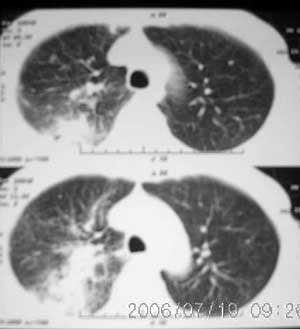

以下是引用jiangjing在2006-7-20 19:22:00的发言:[br]右侧肺门见有软组织肿块,边缘不规则,不光整,其周围肺内见炎性片状影,胸片示水平裂呈弧形上移,右上叶支气管狭窄,考虑右肺中央型肺癌伴阻塞性肺炎部分肺不张。

以下是引用1983在2006-7-20 21:53:00的发言:[br]右侧中央型肺癌伴阻塞性肺炎.

以下是引用卜一在2006-7-20 14:13:00的发言:[br]图象质量差了些,首先考虑:中心性肺癌伴阻塞性肺炎.因发生在右肺上叶尖后段,而且外带见二个空洞影,次考虑:不排除肺结核